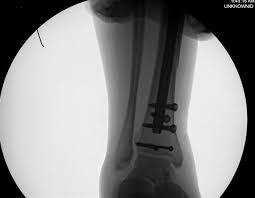

Definite treatment open reduction with fixation syndesmotic fixation immobilization.

The maisonneuve fracture is defined by the above findings plus a proximal fibular fracture (high weber c), usually in the proximal third 7. This study reviewed operative treatment of maisonneuve fracture of the fibula in 26 patients. Case courtesy of dr roberto schubert, radiopaedia.org. Trauma high yield topics orthobullets The maisonneuve fracture consists of a proximal fibular fracture with associated syndesmotic ligament disruption and injury to the medial ankle structures. Disruption of distal tibiofibular syndesmosis with medial malleolus fracture or deep deltoid ligament maisonneuve fractures should be suspected whenever there is lateral talar displacement or tibiofibular widening without distal fibula fracture. Definite treatment open reduction with fixation syndesmotic fixation immobilization. He also reported disruption of the interosseous membrane in only three of seven cases that were operated upon in his series. The maisonneuve fracture is a spiral fracture of the proximal third of the fibula associated with a tear of the distal tibiofibular syndesmosis and the interosseous membrane. Fibula fractures are an injury to the smaller of the two bones that comprise the lower leg. Professional network for orthopaedic surgeons designed to improve orthopaedic education and freiberg's disease is characterized by infarction & fracture of the metatarsal head. Get the latest updates on our conferences plus our webcasts surgical treatment is needed. Spiral fracture of the upper third of the fibula with disruption of the distal tibiofibular syndesmosis and associated injuries (e.g., fracture of the medial malleolus, fracture of the posterior 1.

Extern conference by chawanin lerspongpaibool ramathibodi 5402029. There is an associated fracture of the medial malleolus or rupture of the deep deltoid ligament. A maisonneuve fracture is caused by pronation and external rotation. Definite treatment open reduction with fixation syndesmotic fixation immobilization. This study reviewed operative treatment of maisonneuve fracture of the fibula in 26 patients.